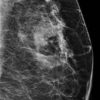

Ung thư vú

» Thông tin: Nữ giới – 42 tuổi.

» Lâm sàng: Kiểm tra sức khỏe.